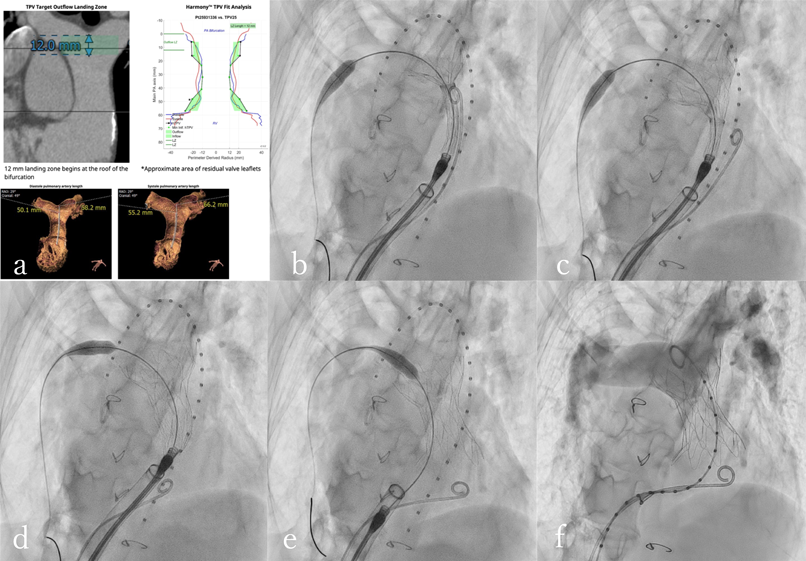

【ABL/カテ検査】 検査・治療|循環器内科|大阪市立総合医療センター循環器センターの詳細情報

検査・治療|循環器内科|大阪市立総合医療センター循環器センター。神戸アドベンチスト病院 | カテーテル検査・治療。Argyle™ Fukuroi CV カテーテル セルジンガー キット。あんず⚠︎2冊とも裁断済みです⚠︎これから始める カテーテルアブレーションこれから始める 心臓カテーテル検査発送は7/11となります。ACHDのカテーテル治療:現在まで,そして未来へ。よろしくお願い致します。病気がみえる vol.3 糖尿病・代謝・内分泌。